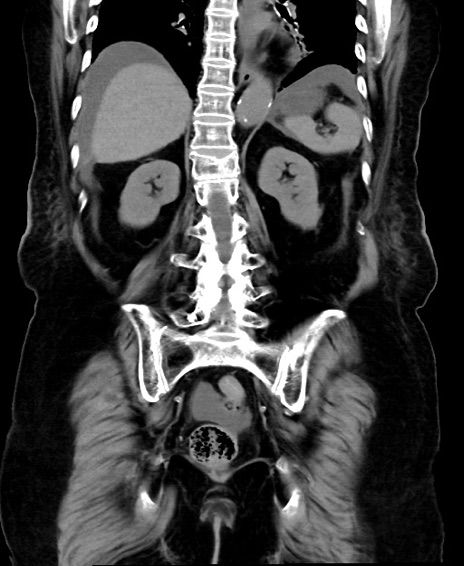

【症例】90歳代女性

【主訴】腹痛・嘔吐

【現病歴】 食欲低下、嘔吐があり昨日他院受診。肺炎と診断され入院となる。入院後より腹部全体に圧痛あり。胃管留置され経過みていたが、症状持続するため、

当院転院となる。

【既往歴】胸椎圧迫骨折、胆石症

【身体所見】腹部:中央に激痛あり、圧痛あり、反跳痛不明

【データ】WBC 17100、CRP 18.82